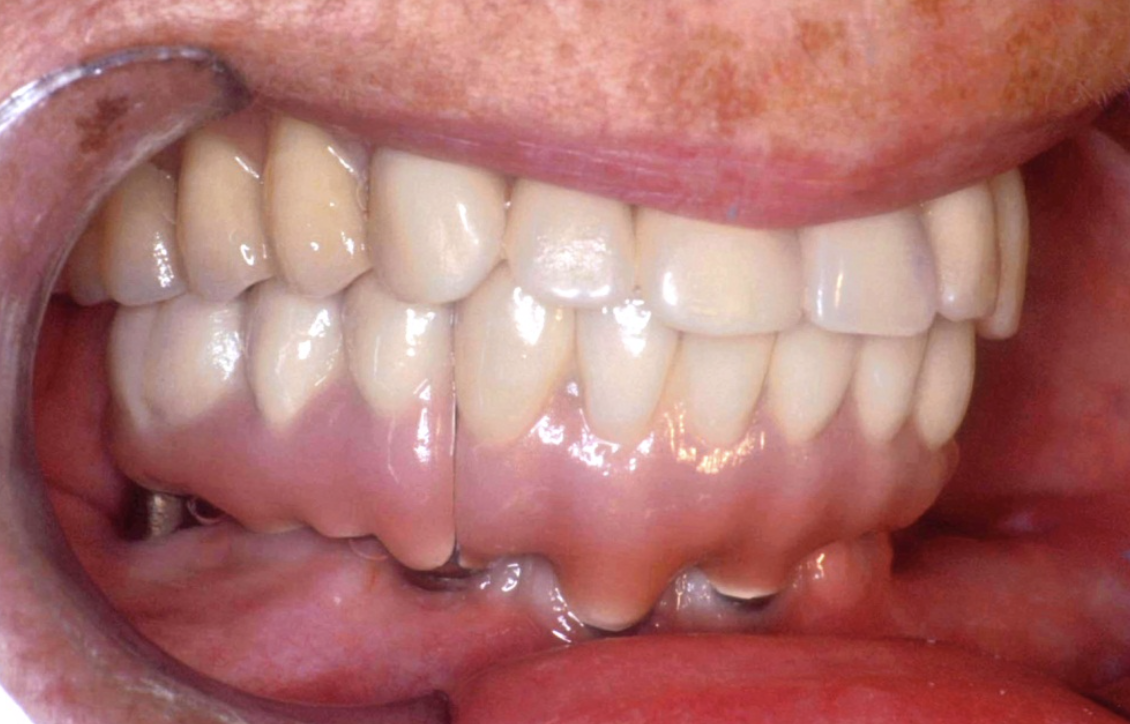

Patient Factors that May Contraindicate Fixed Implant-supported Prosthetics

(42.) Fixed-removable prosthesis.

Figure 42

(43.) Fixed-removable prosthesis.

Figure 43

(44.) Fixed-removable prosthesis.

Figure 44

(45.) Fixed-removable prosthesis.

Figure 45